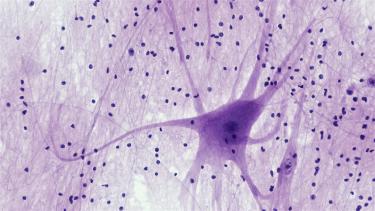

How Gut Microbiome Changes Directly Influence Brain Function

Discover how the gut brain connection shapes mental health through serotonin production, the vagus nerve, and microbiome signaling.

Your gut and your brain are in constant conversation. Most people don’t realize that roughly 90% of the …